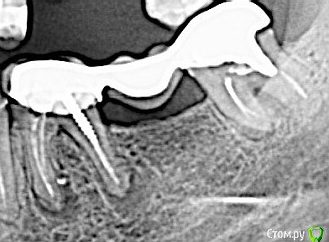

полосатая Опубликовано 24 октября, 2016 Автор Поделиться Опубликовано 24 октября, 2016 тогда имеет смысл поискать Врача http://forum.stom.ru/topic/4752-posovetujte-terapevta-v-gorode-n/page-38Благодарю.Скажите пожалуйста, а в 8-м нужно делать ревизию? Мне кажется ( я конечно не доктор),но на снимке на верхушках корней также видны темные пятна, это гранулемы?P.S. Добыла у друзей - коллег контакты их стоматологов.Но на этой неделе никто не сможет принять, время у всех расписано. Послезавтра приезжает мой врач. Что посоветуете? Ссылка на комментарий

red_butler Опубликовано 24 октября, 2016 Поделиться Опубликовано 24 октября, 2016 Прошу, по возможности напишите подробнее, что с этим зубом не так . потеря костной ткани между корнями, степень разрушения вообще использование зубов мудрости как опору мостовидного протеза не лучшее решение Ссылка на комментарий

IvanK Опубликовано 25 октября, 2016 Поделиться Опубликовано 25 октября, 2016 мне кажется, что уже пора удалить 6 и 8 и поставить имплантаты 6 и 7 1 Ссылка на комментарий